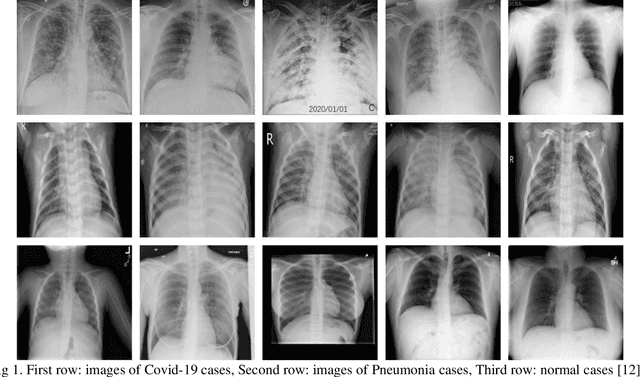

Abstract:Du e to rapid population growth and the need to use artificial intelligence to make quick decisions, developing a machine learning-based disease detection model and abnormality identification system has greatly improved the level of medical diagnosis Since COVID-19 has become one of the most severe diseases in the world, developing an automatic COVID-19 detection framework helps medical doctors in the diagnostic process of disease and provides correct and fast results. In this paper, we propose a machine lear ning based framework for the detection of Covid 19. The proposed model employs a Tsukamoto Neuro Fuzzy Inference network to identify and distinguish Covid 19 disease from normal and pneumonia cases. While the traditional training methods tune the parameters of the neuro-fuzzy model by gradient-based algorithms and recursive least square method, we use an evolutionary-based optimization, the Cat swarm algorithm to update the parameters. In addition, six texture features extracted from chest X-ray images are give n as input to the model. Finally, the proposed model is conducted on the chest X-ray dataset to detect Covid 19. The simulation results indicate that the proposed model achieves an accuracy of 98.51%, sensitivity of 98.35%, specificity of 98.08%, and F1 score of 98.17%.